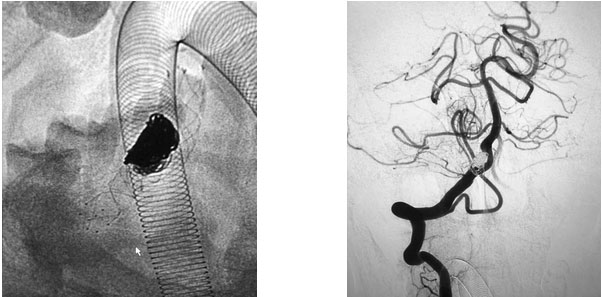

在充分準(zhǔn)備后,張琪博士在劉春醫(yī)生、周林華醫(yī)生協(xié)助下為患者進(jìn)行了支架輔助動(dòng)脈瘤栓塞手術(shù)。填入彈簧圈后,再置入支架,完全釋放后,造影顯示動(dòng)脈瘤無顯影,支架覆蓋良好,載瘤動(dòng)脈通暢,撤出微導(dǎo)管輸送系統(tǒng),復(fù)查雙側(cè)椎動(dòng)脈造影顯示遠(yuǎn)端血流通暢。

▲ 術(shù)后,造影顯示動(dòng)脈瘤無顯影,栓塞成功